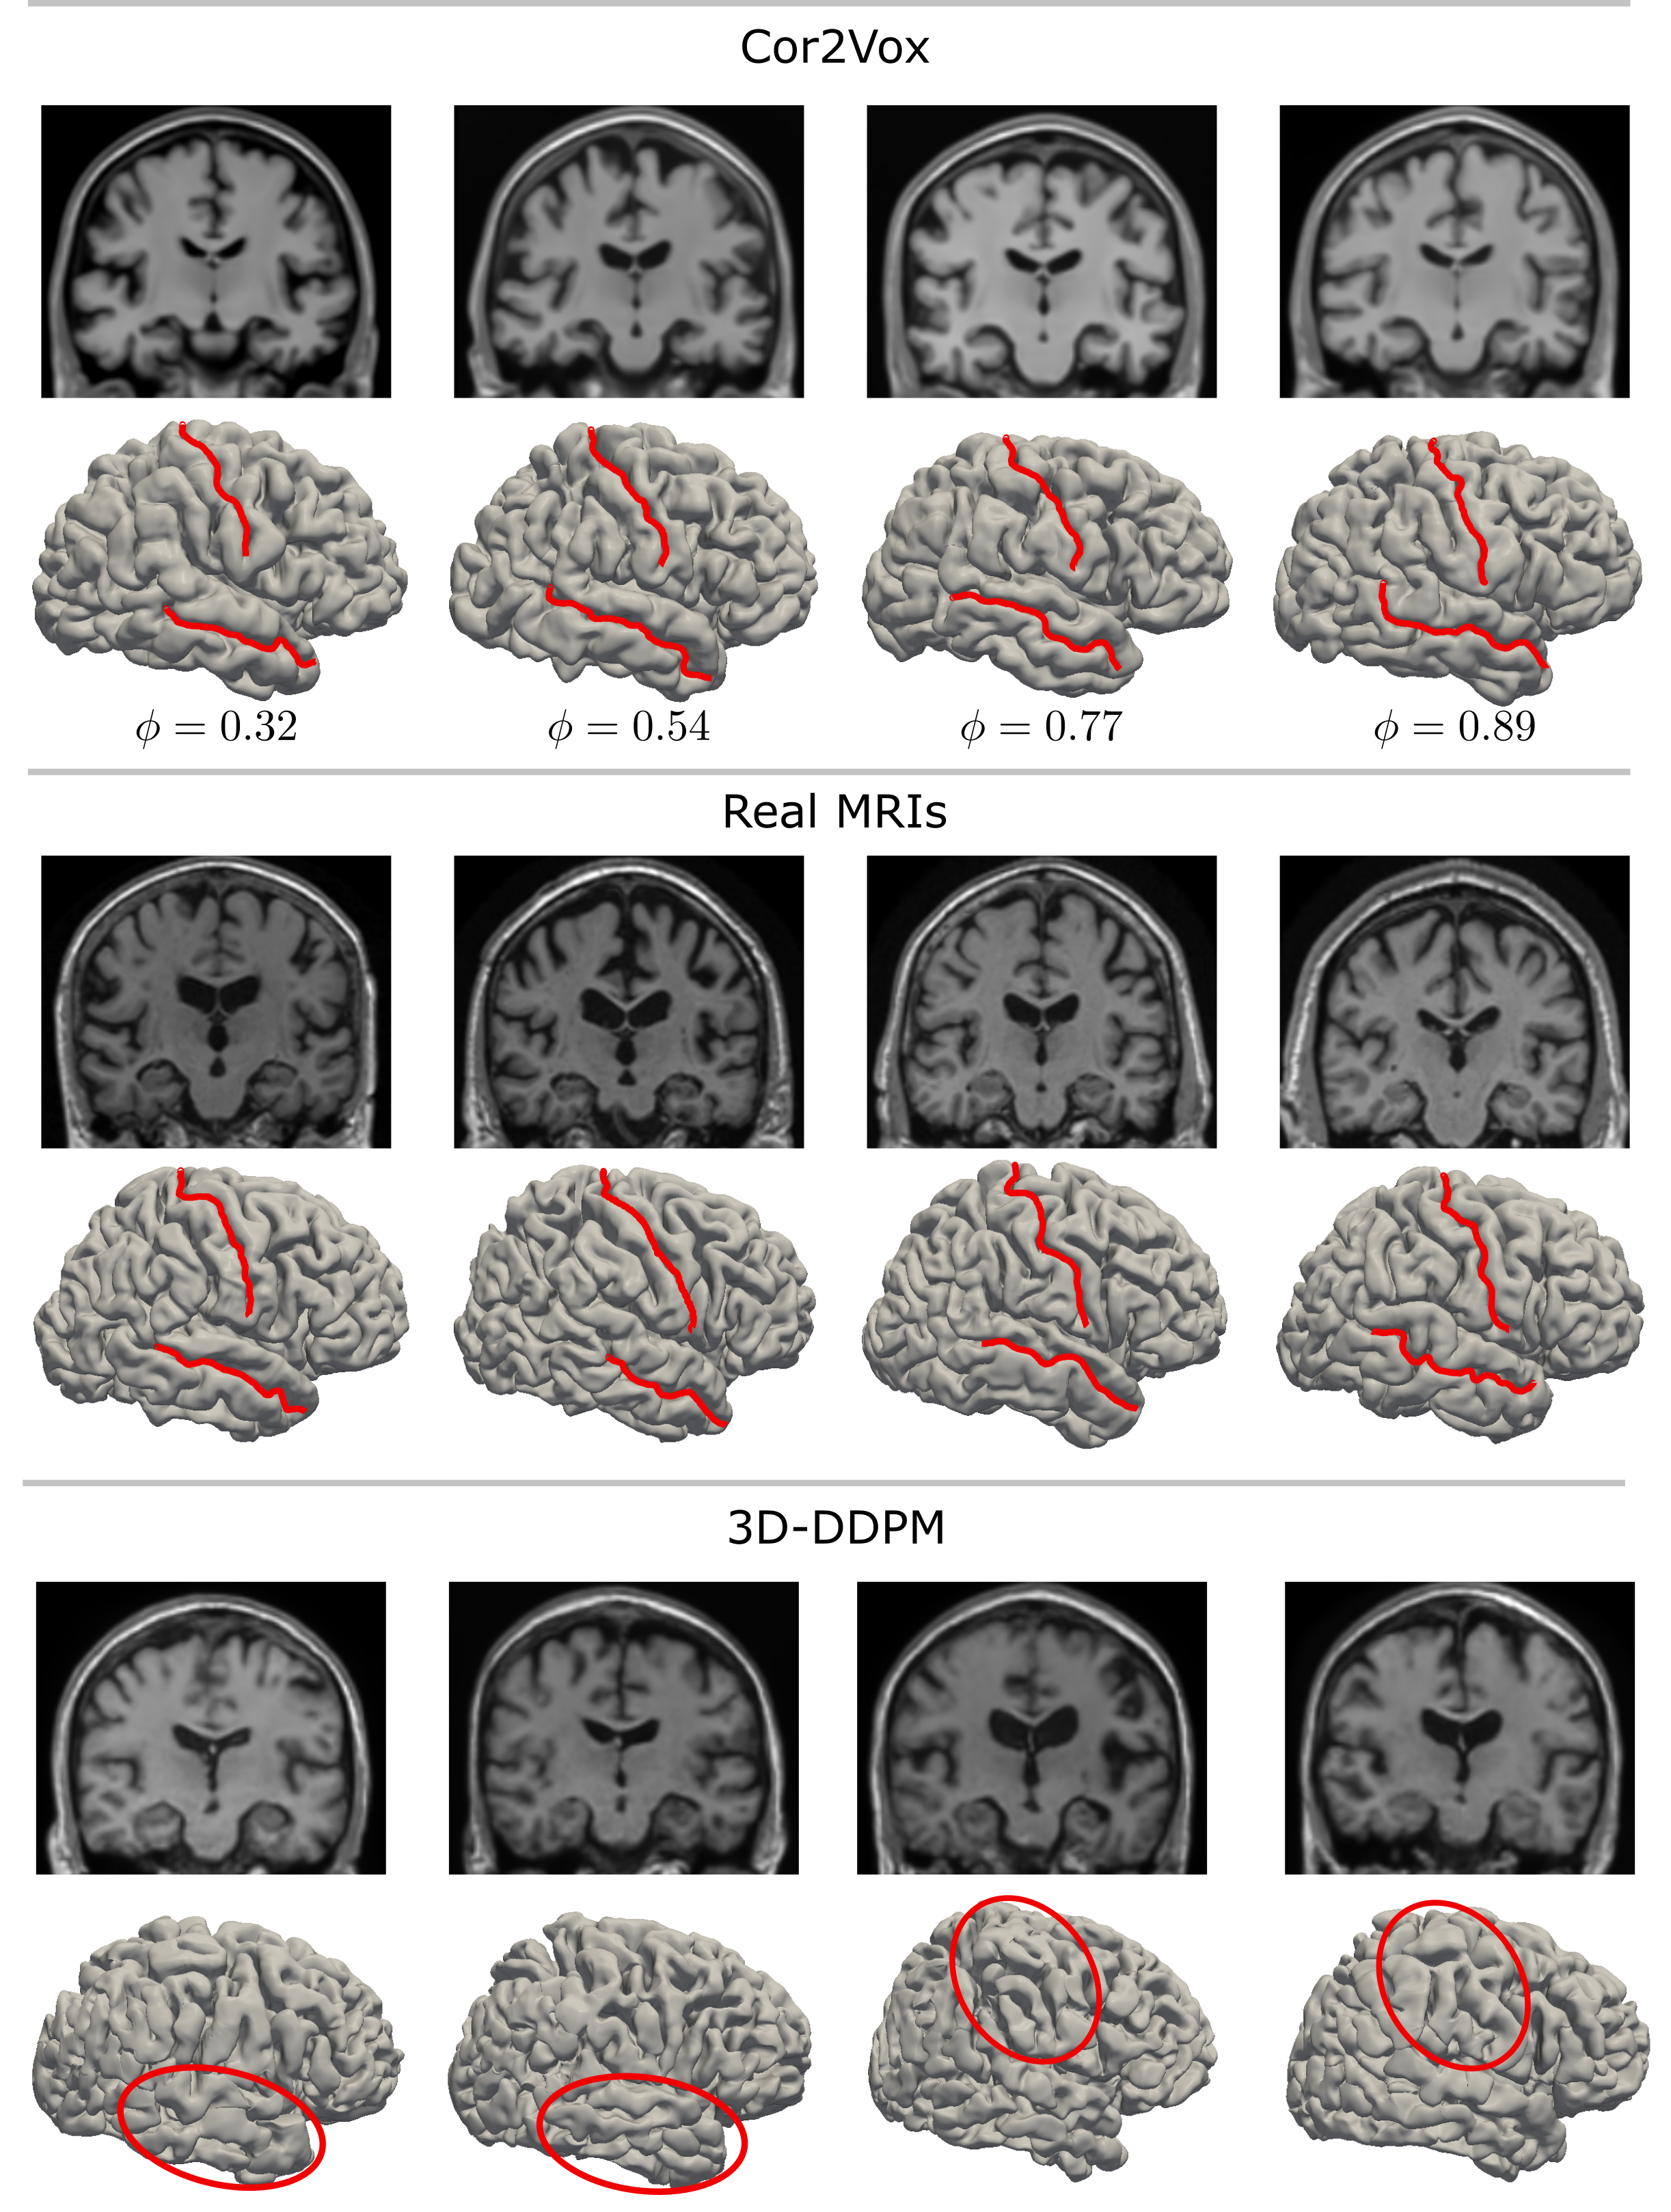

Figure 1: Synthetic MRIs generated by Cor2Vox (top) and 3D-DDPM (bottom), with real MRIs shown for reference (center). Cortical surfaces were reconstructed from the MRIs using Vox2Cortex-Flow. Red lines indicate the central sulcus and superior temporal sulcus, two prominent cortical grooves in human brain anatomy. While Cor2Vox reliably preserves these sulci, they are often absent or significantly distorted in surfaces reconstructed from MRIs generated by 3D-DDPM. Such anatomical irregularities are virtually impossible to detect in conventional 2D slice-based views and require 3D surface reconstructions for reliable assessment. ϕ(0,1)\phi\in(0,1) denotes the spherical interpolation factor in the Cor2Vox shape model.

Synthetic data can overcome the persistent limitations of real-world medical datasets, such as the limited availability of rare phenotypes, the heterogeneity of imaging devices that introduces domain shifts, and the scarcity of longitudinal data required for disease progression modeling [54]. Despite these advantages, current approaches to medical image generation predominantly rely on implicitly learned associations between low-dimensional labels or short text and high-dimensional image observations [51, 29, 31, 53, 41, 56]. This paradigm lacks explicit control over generated content, making it susceptible to undesired bias [34], memorization of sensitive training data [11], model collapse [47], and implausible hallucinations [52]. In neuroimaging, these challenges are amplified by the complexity of the cerebral cortex, which is inherently difficult to model due to its intricate folds and grooves. Structural inaccuracies and hallucinations often go unnoticed in conventional 2D visualizations and image-based metrics (see Figure 1).

Our study revealed flaws in conventional DDPMs [24], arguably the de facto standard architecture for high-dimensional image generation, when applied to unconditional 3D brain image generation, cf. Section 3.2. Specifically, we found that 3D-DDPMs do not preserve characteristic grooves in the cerebral cortex, such as the central and superior temporal sulci. These irregularities break standardized atlas-based brain parcellation, which is crucial for many downstream neuroscience applications [36]. Our findings align with prior work advocating for rigorous evaluation of synthetic brain MRIs [57], extending these efforts beyond volume-based metrics such as Cohen’s d to include advanced cortical surface reconstruction. In Cor2Vox, we addressed these issues by incorporating an explicit shape model of the cerebral cortex. This guarantees anatomical plausibility and, hence, compatibility with surface-based analysis pipelines and standardized parcellation schemes.

The sequence of cortical surfaces in Figure 5a illustrates this process, transitioning smoothly between two arbitrary UKB subjects (see also supplementary video). Importantly, the interpolation preserves both gyrification and cortical thickness, maintaining characteristic cortical grooves, such as the central sulcus, throughout. In contrast, as shown in Figure 1 and Figure S1, 3D-DDPMs failed to maintain such anatomical realism, often producing non-identifiable and discontinuous gyral patterns that hinder subsequent gyral-based parcellation, such as those based on the Desikan-Killiany (DK) atlas [13]. These parcellations are critical for numerous downstream neuroimaging applications. To assess anatomical plausibility, we applied the DK atlas to randomly generated, interpolation-based synthetic cortical shapes and compared regional cortical thickness against real counterparts. The results, summarized in the scatter plots in Figure 5a and Figure S2, demonstrate that Cor2Vox consistently preserves anatomically realistic cortical thickness across all 34 DK regions.